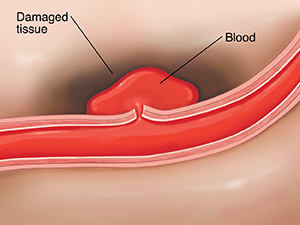

Vessels break

Sometimes, blood flows with enough force to weaken a vessel wall. If the vessel is small or damaged, the wall can break. When this happens, blood leaks into nearby tissue and kills cells. Other cells may die because blood cannot reach them.